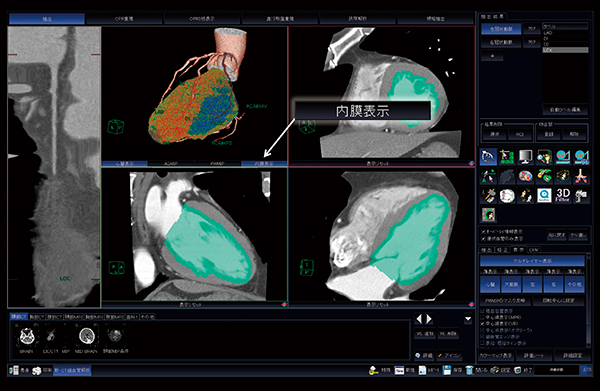

VirtualPlaceによる解析方法

新・CT細血管解析では,画像を読み込むと大動脈,心臓,左右の冠動脈を自動で抽出できる。従来では心臓の全体像を抽出していたが,新たな機能として左室心内膜のみを自動抽出することが可能になった。方法はとても簡単であり,内膜表示というボタンをクリックするだけで,数秒で心内膜側を三次元的に自動抽出し,心筋のCT値を反映したカラーマップでVR表示される(図2)。虚血は,心内膜側から起こり心外膜側に進展するため,内膜側を選択的に抽出することで正常領域と灌流異常領域に明瞭なコントラストを得られ,虚血に対する診断能が上がる。さらに,冠動脈と左室心内膜側のVRを融合表示することで,灌流異常の評価とともに病変部の責任血管を容易に同定でき,一連の流れで冠動脈の形態的評価と心筋の機能的評価を行うことが可能である。

図2 心内膜カラーマップ表示機能イメージ